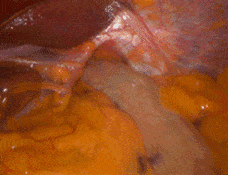

A hiatal hernia occurs when the upper part of the stomach pushes through the diaphragm into the chest cavity through a widened esophageal opening (hiatus). This opening, normally teardrop-shaped, can become dilated, allowing stomach contents to move upward, often causing or worsening symptoms of gastroesophageal reflux disease (GERD).

Hiatal hernia repair is typically performed laparoscopically under general anesthesia. The procedure involves reducing the hernia, tightening the diaphragm’s opening, and reinforcing the area to prevent recurrence. Most patients only require an overnight hospital stay and can return to normal activities in 5–10 days.